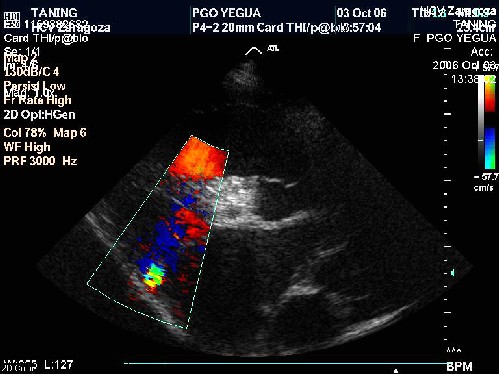

Ecocardiografía

La imagen 1 es un corte de eje largo parasternal derecho. Hay dilatación o sobrecarga del VD.